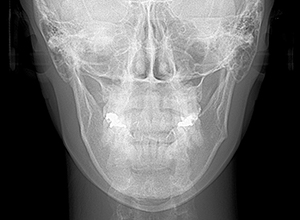

| X-Ray所見 | |

| セファロ所見 | Sellaから下顎頭までの距離は短く、骨体部は大きいが下顎枝の長さが短く、下顎角は開大しているためハイアングルを呈していた。中顔面部の高さは高いため下顎はクロックワイズローテーションをしており前後的にはII級の骨格形態を示していた。 |

| パノラマ所見 | 上下顎左右側8は欠損していた。 |